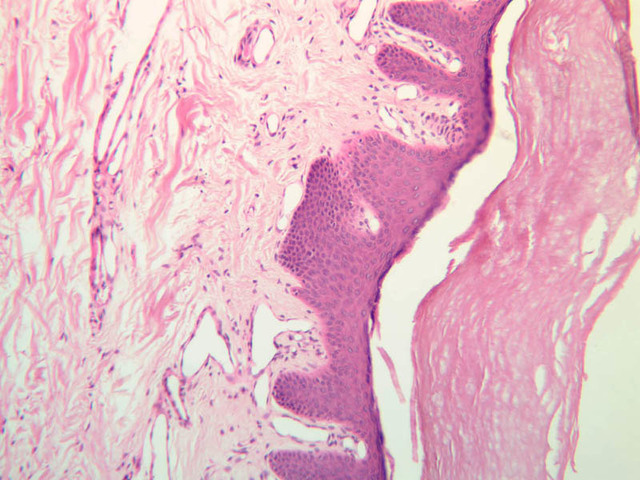

Sebaceous glands (Holocrine)

These glands are branched, saccular glands generally associated with hair follicles (slide A-48, abdomen [2.5x, 10x-labeled, 20x, 40x] [2.5x, 10x, 20x, 40x] [2.5x, 20x, 40x]). They can be seen on the skin side of the lip (slide A-55 [2.5x, 10x]) and in the scalp (A-52 [2.5x, 10x]; A-59 [10x] [2.5x, 10x]). The gland consists of a shell of viable epithelial cells externally which gradually undergo fatty degeneration as they are pushed into the interior of the gland. They finally disintegrate completely and form the fatty substance that makes up sebum. This material leaves the gland through its neck which attaches to a hair follicle.

Locate a hair follicle cut in cross section (slide A-49, embryo scalp [2.5x, 10x, 20x, 40x] [2.5x, 10x, 20x-labeled, 40x]; A-59, scalp [2.5x, 10x, 20x, 40x]; A-58, axilla [10x, 20x, 40x-labeled]). It will have the appearance of a series of concentric rings. The outermost ring is a layer of condensed connective tissue. Interior to the connective tissue can be seen the thickened basement membrane of the hair follicle. Inside the basement membrane is the epithelial root sheath. Cells in the outer part of the root sheath are non-keratinized and appear clear; cells of the inner root sheath are keratinized and form a cuticle with cells overlapped downwards. The hair shaft lies inside the epithelial root sheath. The shaft cuticle consists of keratinized cells which overlap upwards and interdigitate with the follicle cells. Inside the hair cuticle, the cortex of the hair represents the innermost circle. It consists of heavily keratinized, pigmented cells whose individual outlines can no longer be seen. Find a follicle cut longitudinally or obliquely (A-59, scalp [2.5x-labeled, 10x, 20x, 40x, 40x-labeled]). Smooth muscle fibers of the arrector pili muscle are attached to the follicle on the side which forms an obtuse angle with the dermis ([2.5x, 10x-labeled, 20x, 40x] [2.5x, 10x, 20x, 40x]). The arrector pili muscles are small, thin, smooth muscles which are diagonally attached to the hair follicle within the dermis and extend to the epidermis. In the angle formed by the muscle and the hair follicle is located the sebaceous gland. These muscles are under autonomic nervous control (sympathetic).